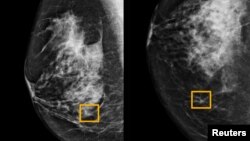

Hình vuông màu vàng cho thấy nơi hệ thống trí tuệ nhân tạo (AI) phát hiện ung thư nằm lẫn trong tế bào vú (ảnh do trường đại học Tây Bắc Chicago công bố ngày 1/1/ 2020)